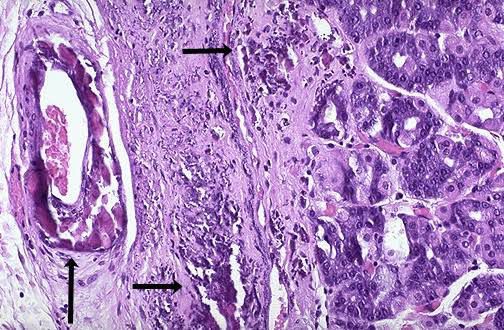

It is characterized by deposition of calcium salt in dead or degraded / degenerated tissue with normal calcium metabolism and normal serum calcium level. It commonly develop in aging or damaged heart valves. The calcium salts microscopically appears as fine, white granules or clumps often felt as gritty deposits. In the pathogenesis of dystrophic calcification the final common pathway is the formation of crystalline calcium phosphate mineral in the form of an apitite similar to an the hydroxyapatite of bone. The process basically has two major phases : Initiation ( or nucleation ) and propagation; both can occur intracellulary and extracellulary.